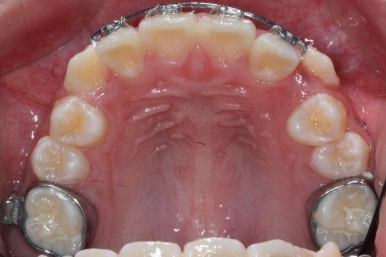

4개월이 지난 모습입니다.

송곳니가 덧니처럼 있었는데 아무것도 안해줬음에도 가지런한 느낌이 훨씬 좋아졌습니다.

공간이 생긴 송곳니는 편안한 위치로 좀 더 서서히 이동을 합니다.

4개월만에 유치가 빠지고 영구치가 조금씩 맹출이 되고 있는 것을 볼 수 있습니다.